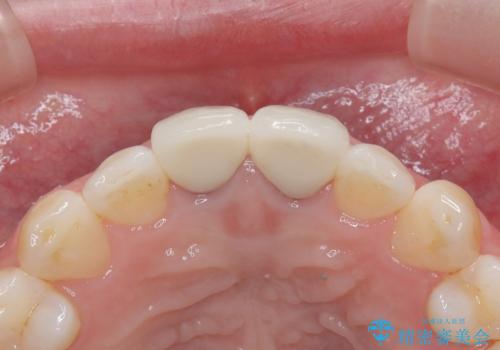

セラミッククラウンで前歯の変色を改善

- 前歯の変色が気になるというご相談をいただき、セラミッククラウンによる治療を行いました。

セラミッククラウンによって前歯の変色が改善され、また歯の形も希望の形態へ修正しました。